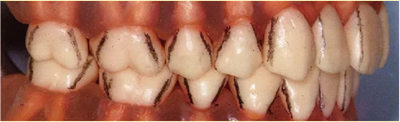

必知要點(diǎn)!注意到分界線

4點(diǎn)法和6點(diǎn)法都是將牙齒分區(qū)進(jìn)行檢測(cè)的,但是牙齒本身是沒有分界線的。

(如下圖所示,在腦中要有牙齒轉(zhuǎn)角處的線條印象。將拐角處的線條延伸至牙頸部紀(jì)委各區(qū)分界線。)